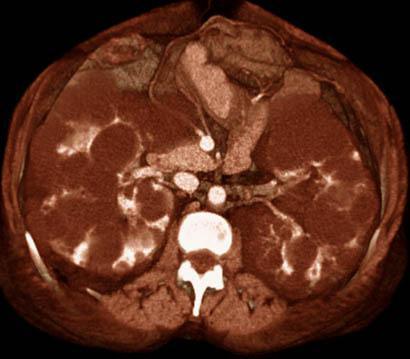

Poliquistosis renal

VR secccional. Visión axial caudal. Múltiples quistes bilaterales provocando un aumento de tamaño de ambos riñones